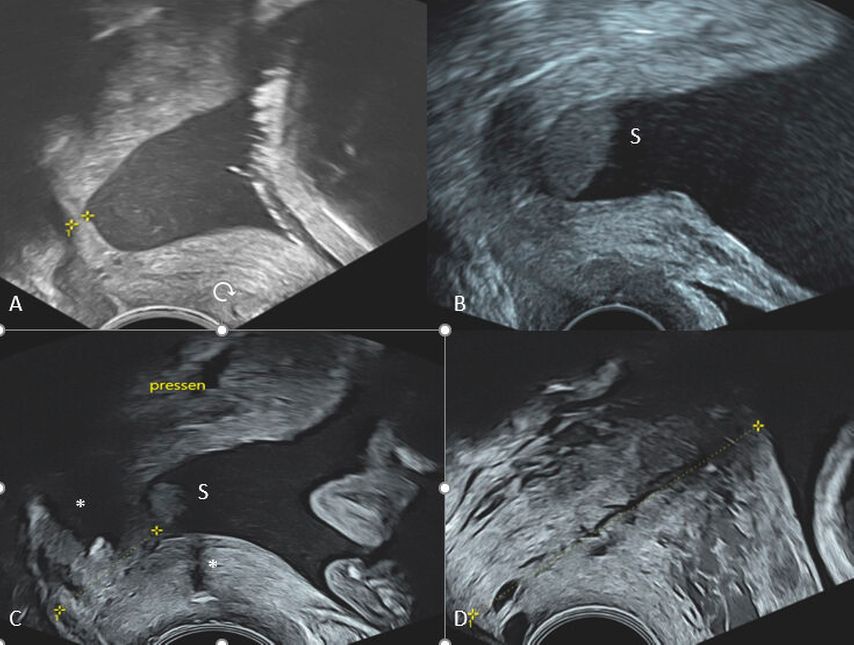

Die Messung der ZXL erfolgt durch die Platzierung der Messkreuze am inneren und am äusseren MM. Gemessen wird in einer geraden Linie zwischen beiden Messpunkten und – trotz Krümmung der Zervix – nicht in zwei Segmenten. Die Zervix ist in 51% der Fälle bei einer Länge >25mm gekrümmt und immer gerade, wenn die ZXL <16mm beträgt. Insofern ist eine gerade Zervix immer verkürzt. Bei der Bildung eines Trichters wird das Messkreuz an die Spitze des Trichters gesetzt. Der Trichter selbst wird nicht gemessen (Abb.2).

Identifizierung und Beschreibung von Zusatzbefunden

Bei einer Vorwölbung der Fruchtblase in den ZK kommt es zu einer sogenannten Trichterbildung. Jene ändert sich mit zunehmender Verstreichung der Zervix in seinem Aspekt von Y-, V- zu U-förmig. Findet sich eine Trichterbildung, wird die Restzervix gemessen. Weiterhin kann es zu sogenanntem Sludge kommen (Abb.2). Dieser beinhaltet Eiter, mikrobielle Bestandteile oder feste Partikel wie Vernix und ist mit einer intraamnialen Infektion vergesellschaftet.

Myome, Membranseparation, Plazentationsstörungen, Placenta praevia und Vasa praevia oder aber ein Cerclagefaden können ebenfalls zur Darstellung kommen (Abb.2).

Abb. 2: U-förmiger Trichter (A), Sludge mit Zervixverkürzung (B), Sludge, Trichter und Cerclagefaden * (C),PAS: Placenta-accreta-Spektrum mit verstärkter Vaskularisation (D). S: Sludge, * Cerclagefaden